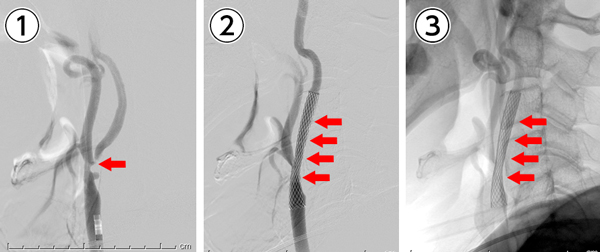

右内頸動脈狭窄症に対して局所麻酔下に頸動脈ステント留置術を施行。手術時間は約30分。

①手術前:右総頸動脈から内頸動脈にかけて高度狭窄を認める(矢印)。

②手術後:右総頸動脈から内頸動脈にステント(金属の筒)が留置され、血管が拡張している(矢印)。

③手術後(骨付き)